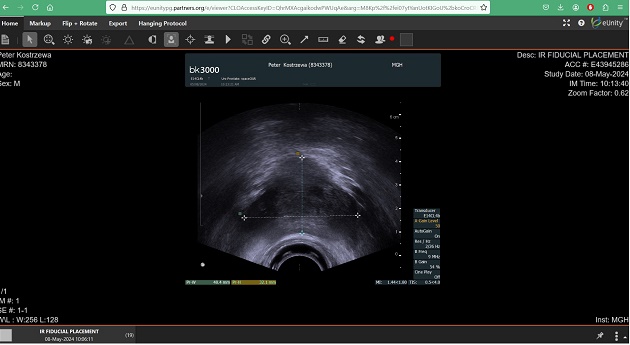

an injection and a prescription for daily pills. After that would be insertion of the gold

markers, or “fiducials,” that would help target the radiation correctly. In addition, an injection of the SpaceOAR rectum-protecting

gel would be performed. All this would

occur within a two-day visit.

Eventually, John was directed to a waiting area with wi-fi where he could do some work. Shortly thereafter, I went in for more bloodwork, then the procedure. After they explained everything they were going to do again, anesthesia was administered and, next thing I knew, I was awake and alert and feeling fine. The process was finished mid-morning and didn’t take as long as they had predicted. Everything was professional and efficient and everyone was nice and friendly. Now I had my gold-plated prostate “goalposts” and injected “butt cushion” and was almost ready for radiation.

After getting my prostate gold-plated, having a seat cushion

injected into my butt and getting an injection of something similar to what they

give to sex offenders, there was just one more thing to do before the start of